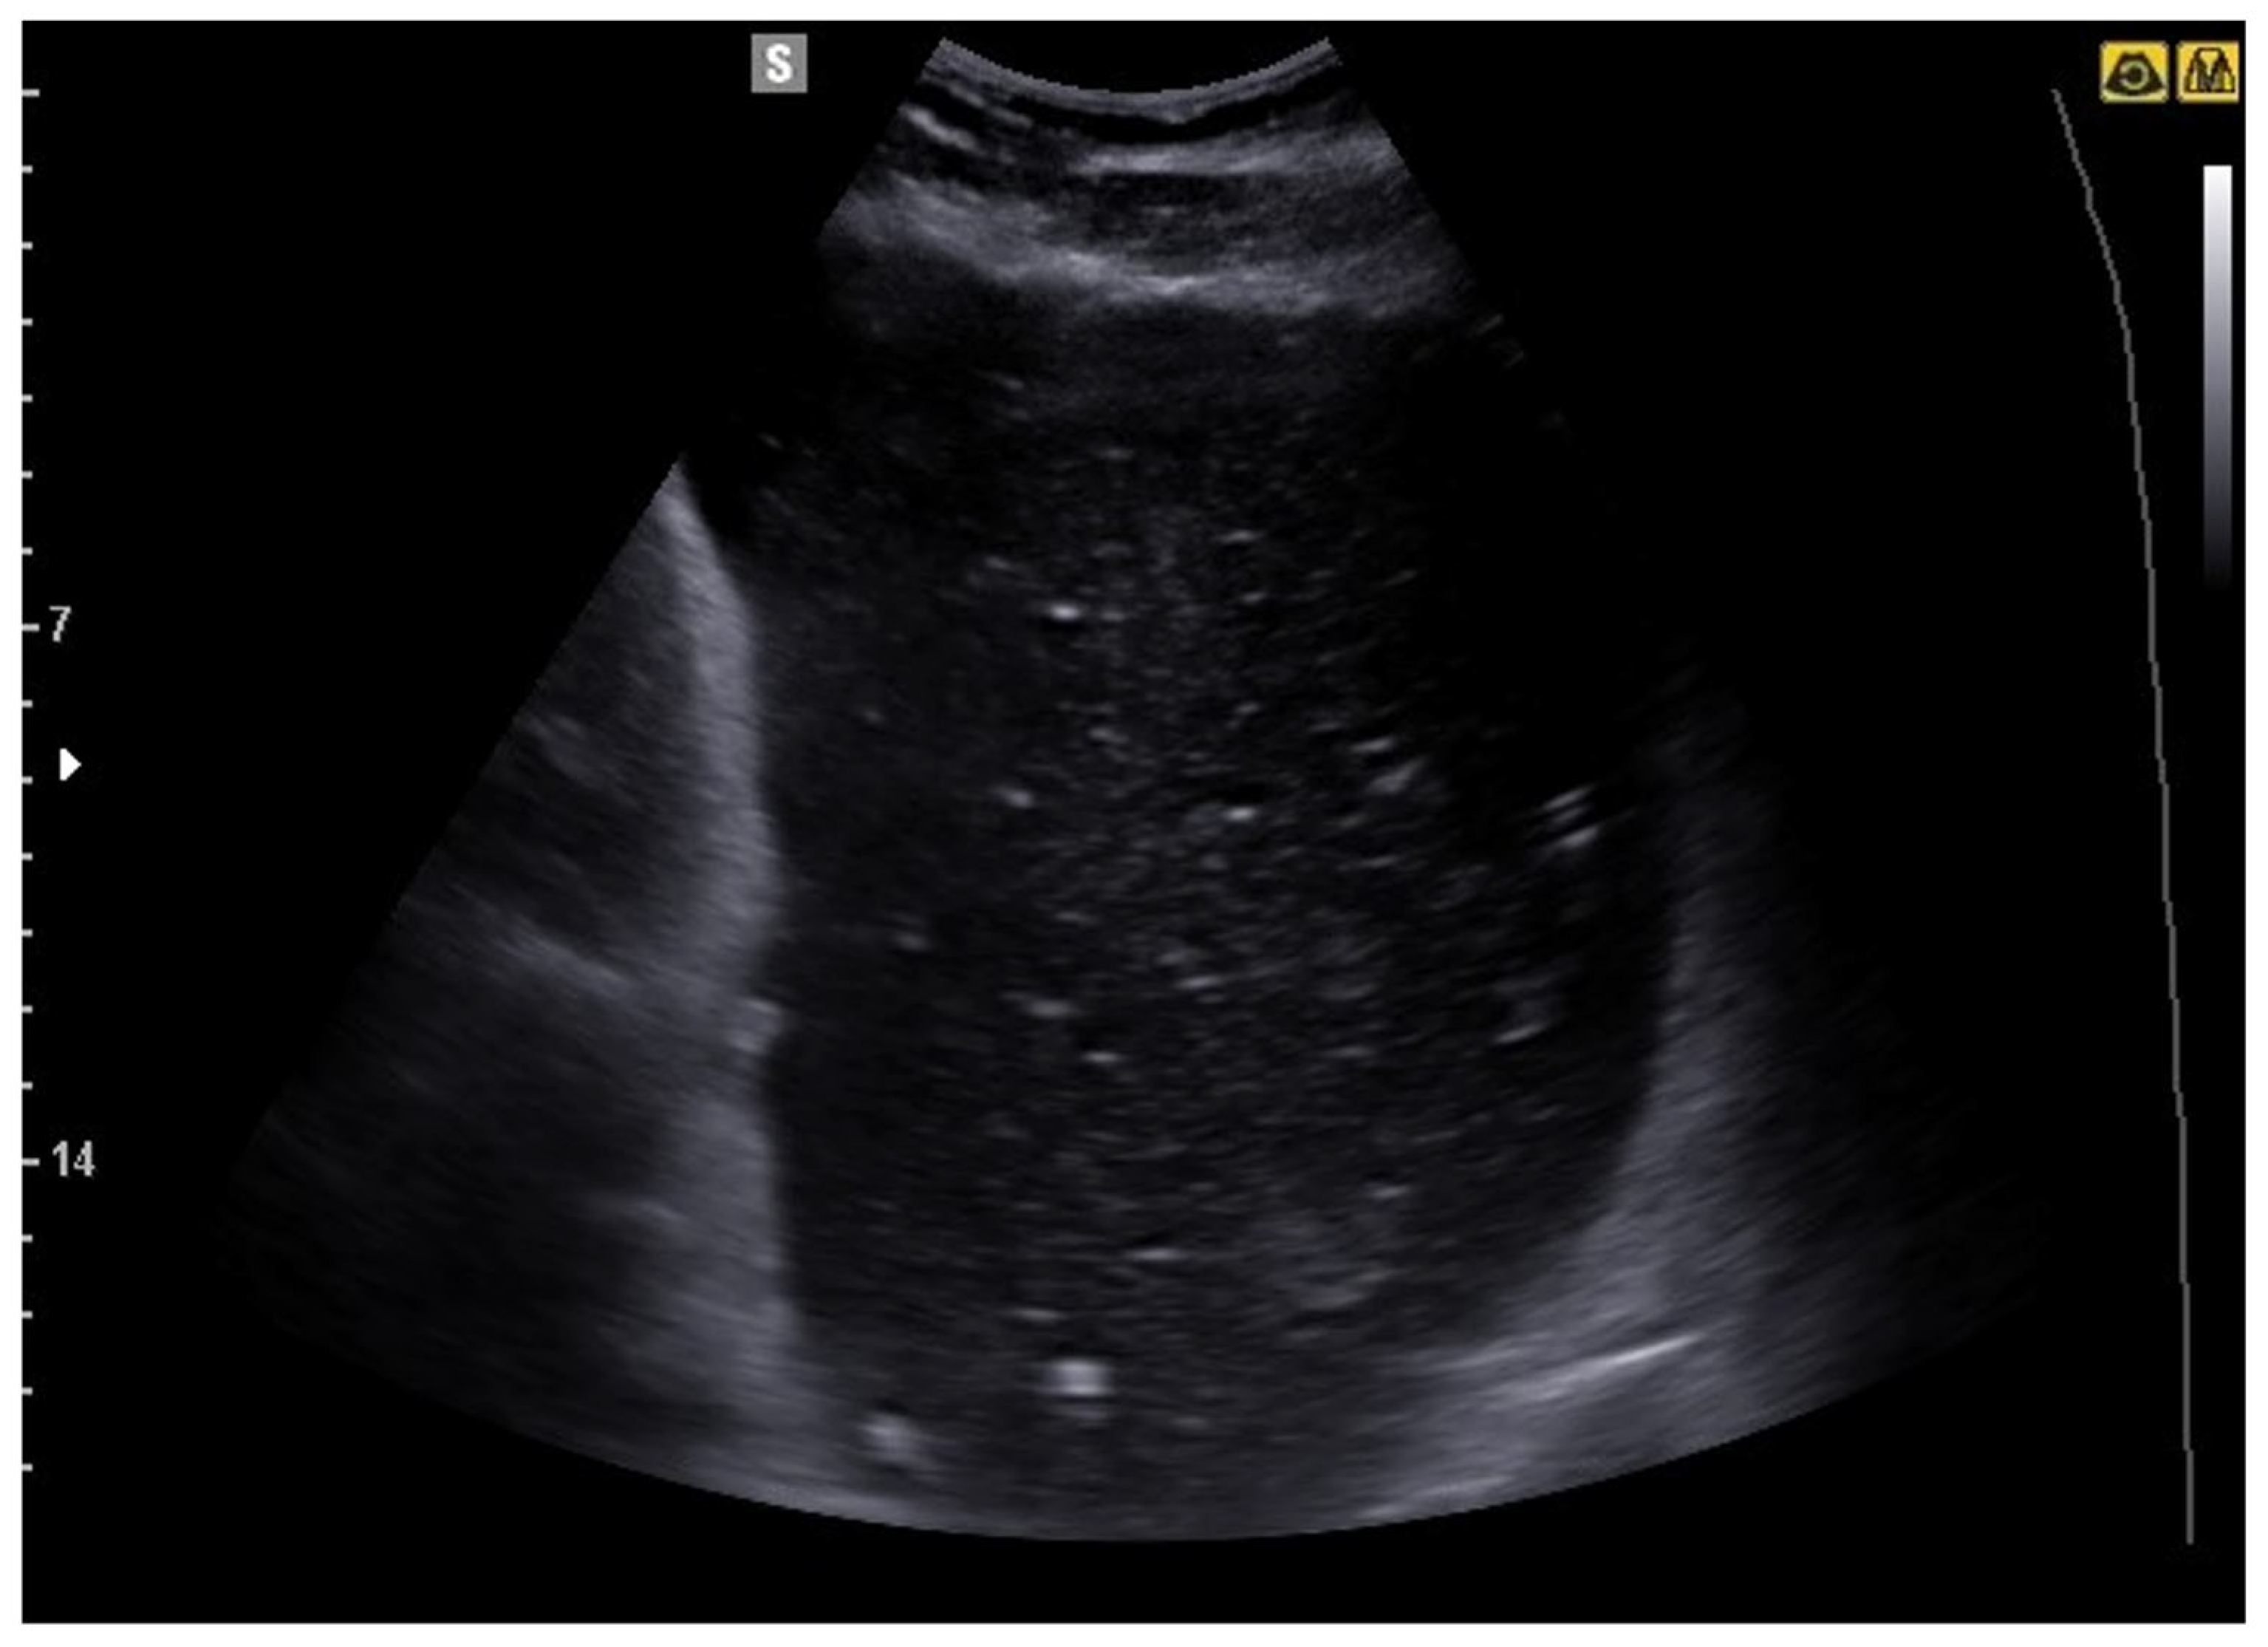

6. Bowel Obstruction

6.1. GIUS Signs of SBO

- Hollerweger, A.; Wüstner, M.; Dirks, K. Bowel Obstruction: Sonographic Evaluation. Ultraschall Med. 2015, 36, 216–235, quiz 36-8. [Google Scholar] [CrossRef]

- Tamburrini, S.; Serra, N.; Lugarà, M.; Mercogliano, G.; Liguori, C.; Toro, G.; Somma, F.; Mandato, Y.; Guerra, M.V.; Sarti, G.; et al. Ultrasound Signs in the Diagnosis and Staging of Small Bowel Obstruction. Diagnostics 2020, 10, 277. [Google Scholar] [CrossRef] [PubMed]